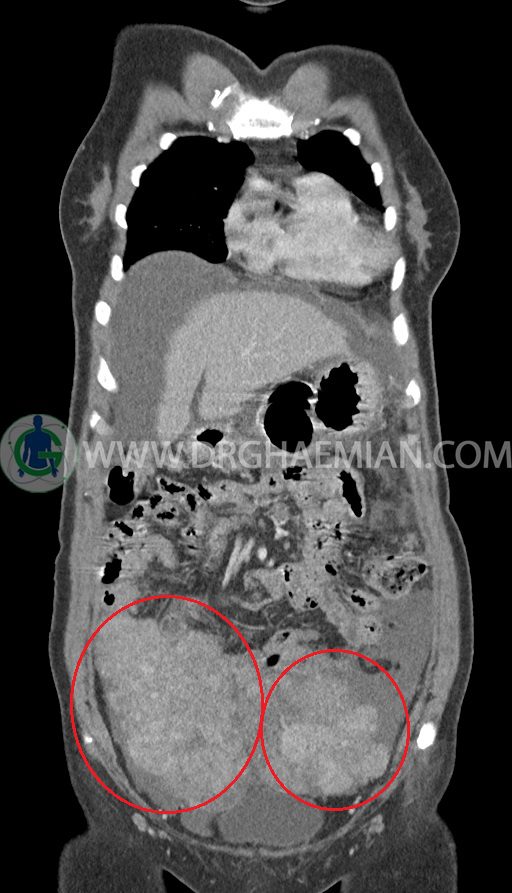

ام آر آی آتروفی عضلانی کتف بیمار

ام ار آی کتف یک روش تصویربرداری است که به وسیله آهنرباهای قدرتمند از قسمت کتف تصاویری ایجاد می کند. این نوع تصویربرداری از تشعشعات استفاده نمی کند. در این کیس آتروفی عضلانی کتف به همراه پارگی تاندون بالاخاری، بورسیت ساب دلتوئید و افیوژن مفصل دیده می شود.

– Complete tearing of supraspinatus tendon with grade 2 retraction and muscle atrophy

– AC joint hypertrophy with subacromial – subdeltoid bursitis

– Glenohumeral joint effusion

are seen.